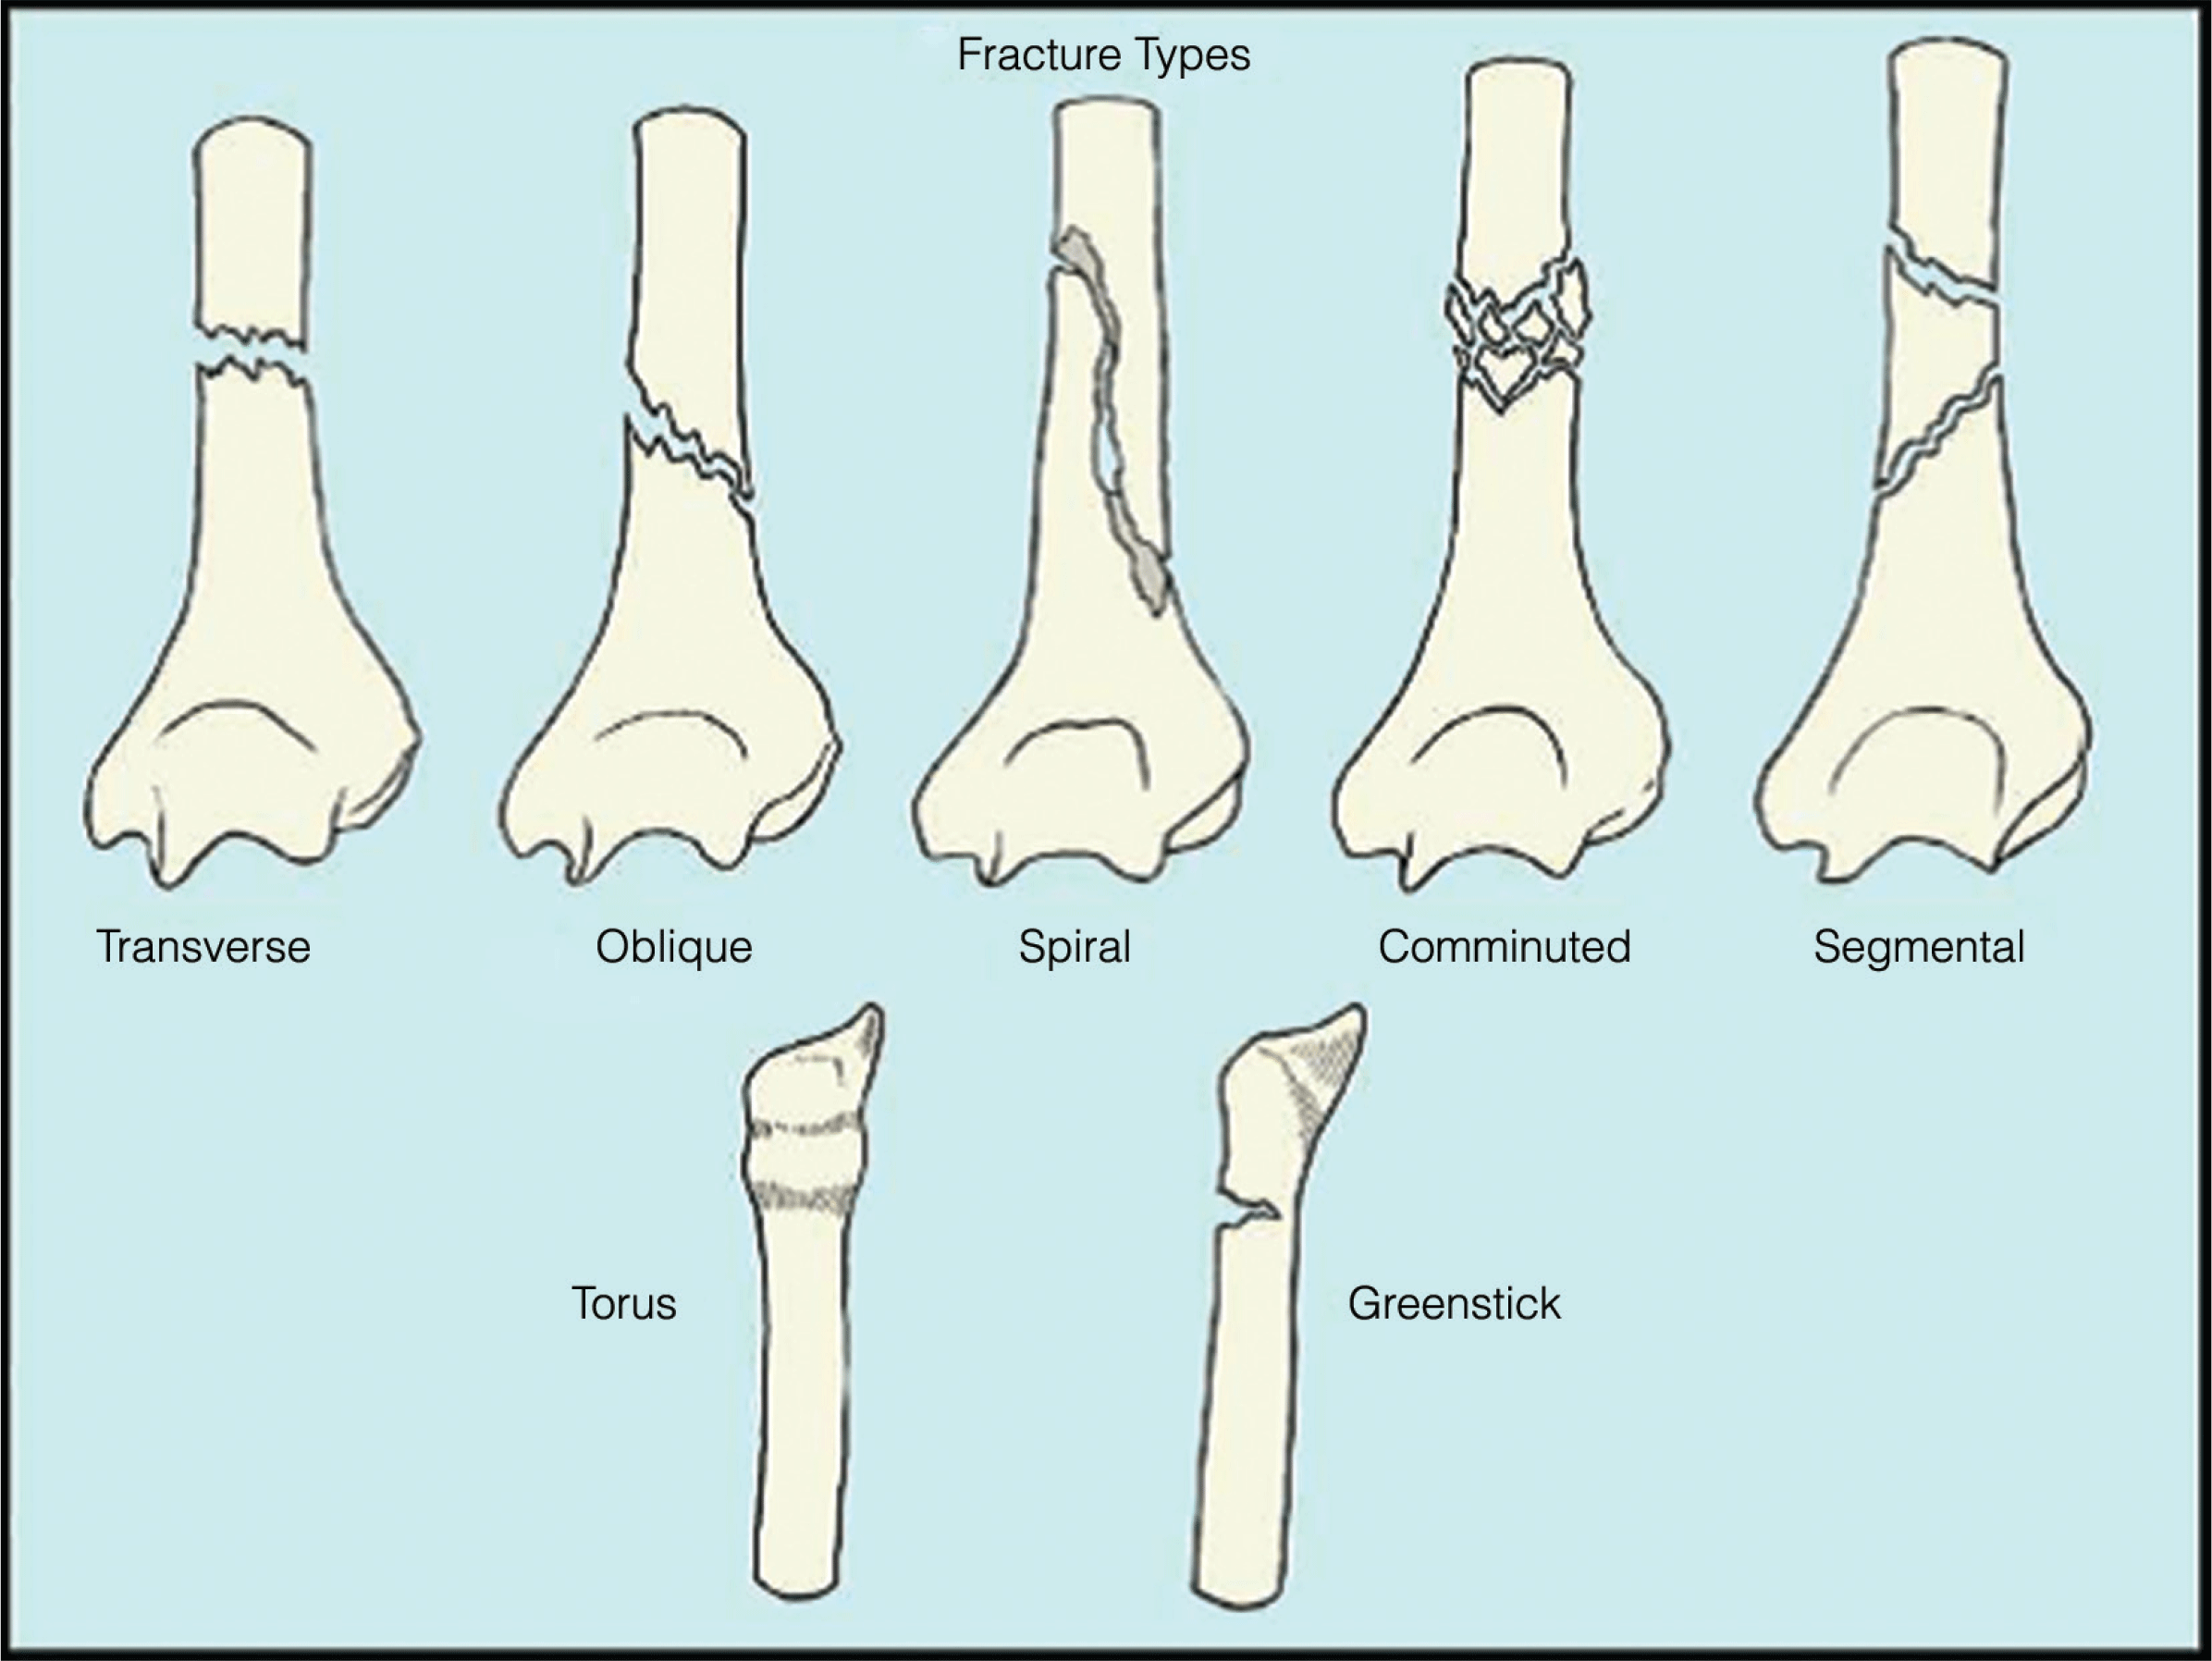

Trauma: Management of Extremity Fractures and Complications